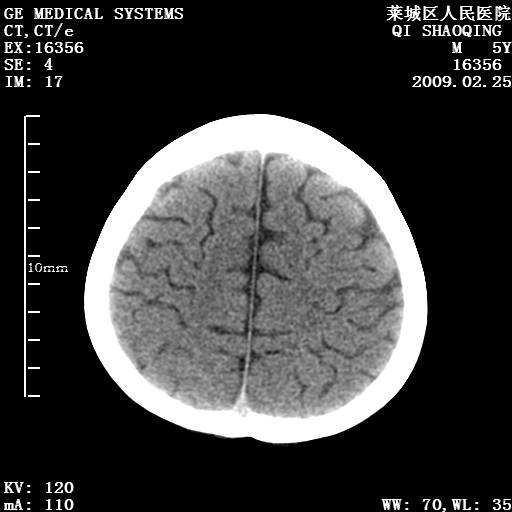

以下是引用wangzhengyuan在2009-2-28 10:22:00的发言:[br]甲状旁腺功能减退引起的脑改变.

以下是引用zsl6918在2009-2-28 10:17:00的发言:[br]首先考虑甲状旁腺功能低下所致,可结合实验室检查明确.另外需除外先天性宫内感染所致.

以下是引用余辉在2009-3-1 9:35:00的发言:[br]患者明显的肢体及智力改变,不支持fahr病,多考虑甲旁低,有可能伴有甲低(呆小症).进一步检查。